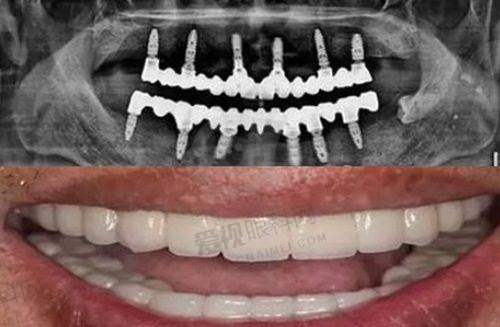

李桂丽医生在牙齿矫正和种植牙领域表现出色。她有着扎实的专精基础和丰富的临床经验,对于疑难种植牙和牙齿畸形问题都有独特的解决方案。无论是复杂的牙齿缺失需要种植牙修复,还是重度的牙齿畸形需要矫正,李医生都能凭借自己的专精能力,为患者制定个性化的治疗方案,帮助患者修复健康美观的口腔状态。

三八路店是一家成立有一定时间的民营口腔诊所,面积达260平方米。它同样经过当地监管部门的认证,提供口腔身体科、外科、正畸、修复、预防保健及颌面外科等多项服务。该诊所位于德州市德城区三八中路860号,地理位置也十分优越。店内设有精良的口腔诊疗设备,其中德国卡瓦口腔CT能够360度扫描口腔内部,为医生提供详细正确的口腔数据,帮助医生制定个性化的治疗方案。在牙齿矫正方面,致美口腔提供多样化的牙齿矫正材料,患者可以根据自己的需求和经济状况进行选择,确保了高性价比。在种植牙方面,院内配备全套德国卡瓦种植系统,能够更正确地判断缺失牙齿的位置及种植角度,支持全口、半口及即刻种植等高难度项目。该诊所是私立机构,但具有正规的营业执照,营业时间为每天08:00至18:00,方便患者前来就诊。